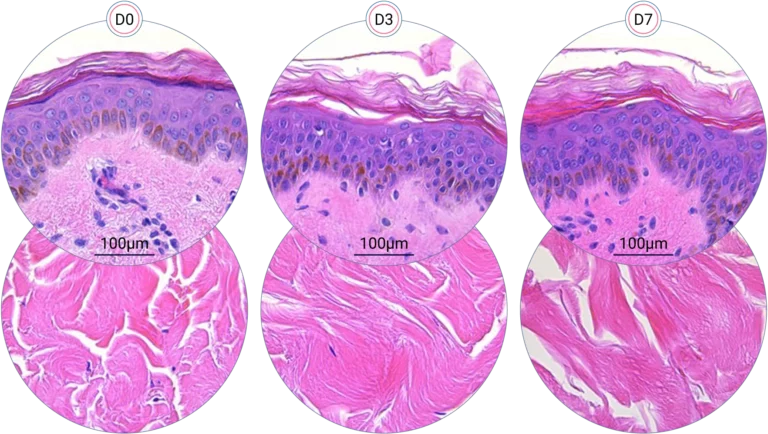

Scientific Validation in Terms of Skin Structure

Human skin structure is maintained for +7 days

Since it is real human skin, NativeSkin® has the same structure and composition as in vivo human skin. It presents a mature stratum corneum and normal skin barrier function and their integrity can be preserved for 7 days. After 7 days of culture, experimental data may show higher variability but NativeSkin® remains viable. Hematoxilin & Eosin staining shows mature stratum corneum, a dermal-epidermal junction that comprises the key features of the dermal-epidermal junction of real human skin, with a preserved basal layer and rete ridges. The images also illustrate that dermis integrity is preserved for 7 days.